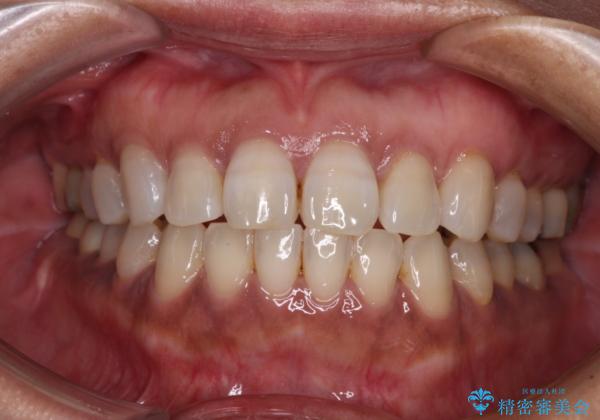

治療前に、いくらインビザライン矯正がオープンバイトを得意としているとは言え、さすがに限界があるだろうと思っておりましたが、前歯でレタスが噛めるまで改善することができました。

顔の印象も大きく変わり、患者様には大変満足していただきました。